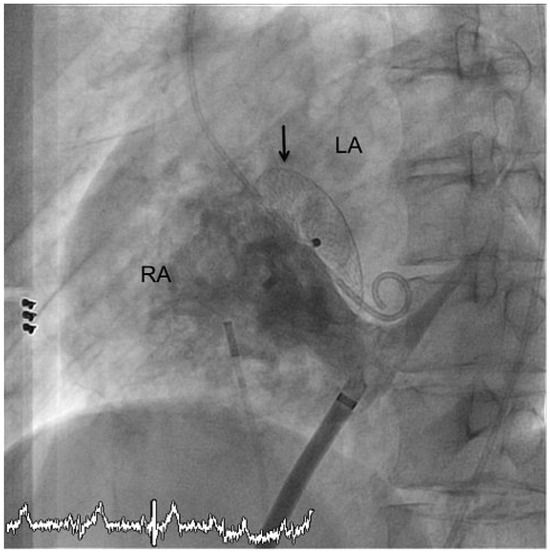

Acute Leriche Syndrome in an 83-Year-Old Man with Non NSTEMI After Cardiac Resuscitation Because of Ventricular Fibrillation

by Daniel Sürder, Jos C. van den Berg, Tiziano Moccetti and Giovanni B. Pedrazzini

An 83-year-old man on permanent haemodialysis was admitted to the emergency department in cardiogenic shock after prolonged electromechanical resuscitation because of ventricular fibrillation [...] Full article